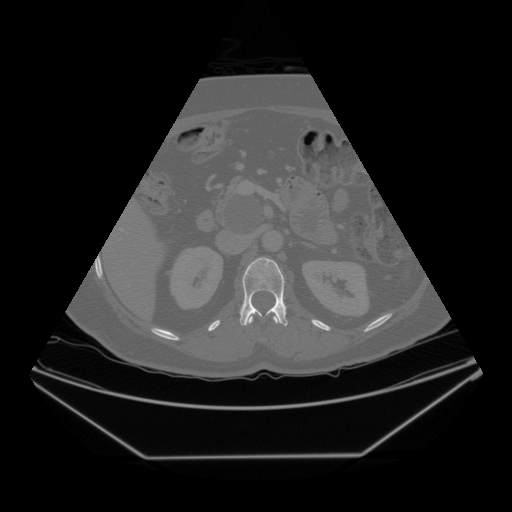

The Abdomen-1K dataset provides more than 1000 CT scans, and the data is provided in 3D format. Firstly, we randomly select 200 CT scans, and for each CT scan, we randomly sampled 10 transverse plane slices. For a more uniform image shape, we applied a fan shape mask to the CT images to mimic the outline of convex ultrasound images.

Fig. 5 and 6 present examples of the translation results from CT to ultrasound. These visual comparisons demonstrate that the S-CycleGAN can not only mimic the ultrasound style but also preserve critical anatomical features compared with Fig. 3. The synthetic images closely resemble real ultrasound scans in terms of texture and shape, suggesting a high level of detail preservation.

Refer to caption

(a) Real CT

(b) Fake US

(c) CT Label

(d) Predicted US Mask

Figure 5: CT-to-ultrasound translation example.1